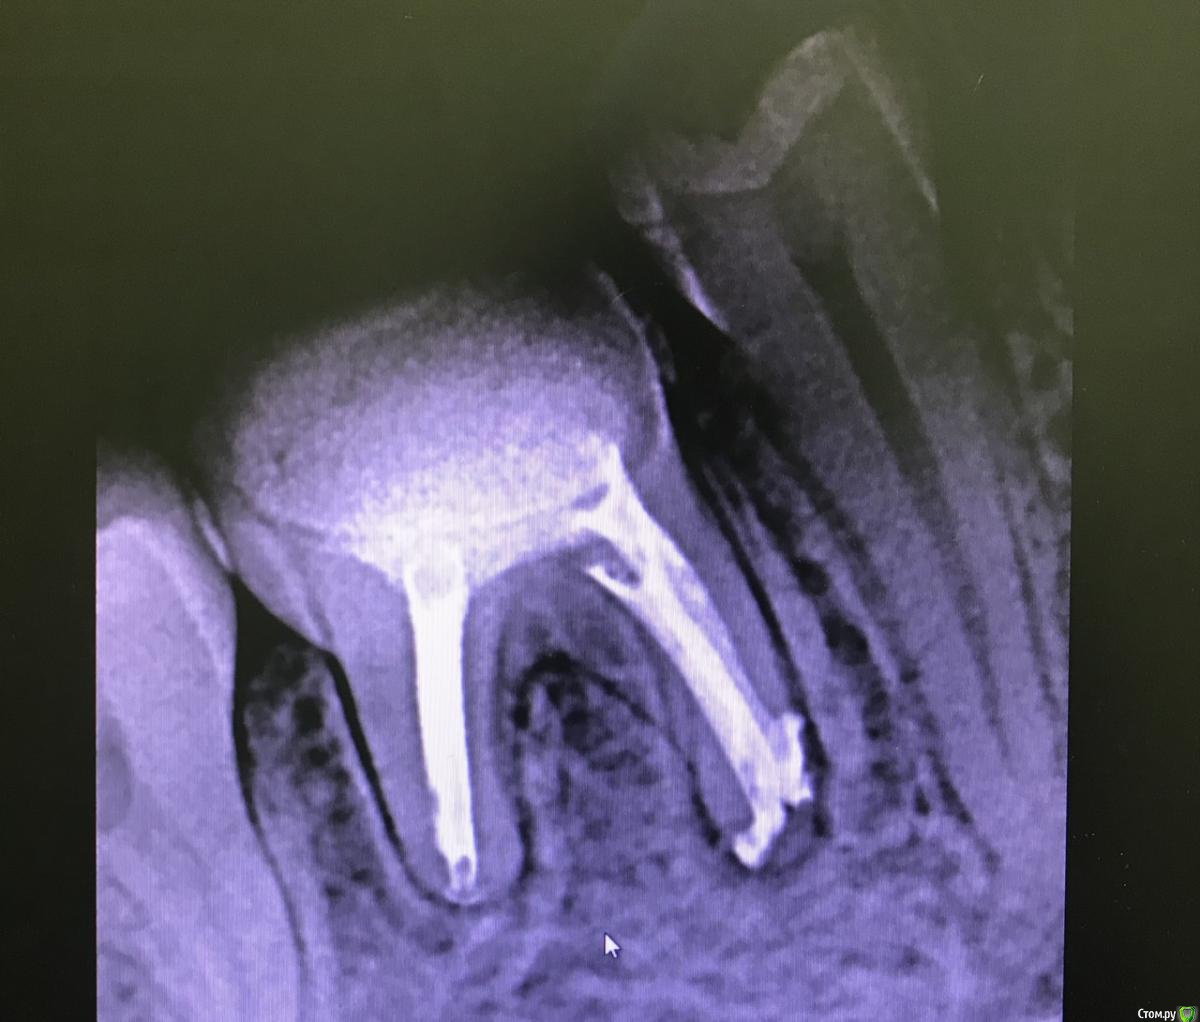

MargaritaEdikovna Опубликовано 22 мая, 2020 Поделиться Опубликовано 22 мая, 2020 (изменено) Здравствуйте, дорогие специалисты!Что вы можете сказать по перелечиванию каналов с кистой на 46 зубе? Правильно ли пролечили?Потому что после установки гуттаперчивых штифтов и постоянной пломбы начались непонятные боли, иногда слабо стреляющие, иногда ноющие, но как будто это десна ноют, иногда как будто распирающие, что хочется его вырвать.Буду благодарна за любые ответы. Изменено 22 мая, 2020 пользователем MargaritaEdikovna 1 Ссылка на комментарий

MargaritaEdikovna Опубликовано 25 мая, 2020 Автор Поделиться Опубликовано 25 мая, 2020 (изменено) Добрый день. После лечения допустим дискомфорт, он постепенно уменьшается и проходит сам по себе. Обычно это несколько дней, но индивидуально может быть и несколько недель. Если же боль со временем не уменьшается или усиливается - нужно показаться своему доктору. Здравствуйте!Доктор говорит, что не знает что болит. Поэтому уже пришлось спрашивать на форуме... При этом я поняла, что боли проявляются такие, как были до лечения. Вот так зуб выглядел до лечения.https://mail.google.com/mail/u/0?ui=2&ik=b2988d84c1&attid=0.1.1&permmsgid=msg-f:1667659142757877677&th=1724b7279a8407ad&view=fimg&sz=s0-l75-ft&attbid=ANGjdJ-QJgKWtcNUCf5zfGscvhc7Amk3aDvF1Yqk1zvwnsxMJgaZJCA2q93AUbnlGDVIvcuu0EEnmFmAcOhvEGSOVn7CKShDuBguQXSLTucTKUIA1ziuP8bS3TDmXr4&disp=emb Изменено 25 мая, 2020 пользователем MargaritaEdikovna Ссылка на комментарий